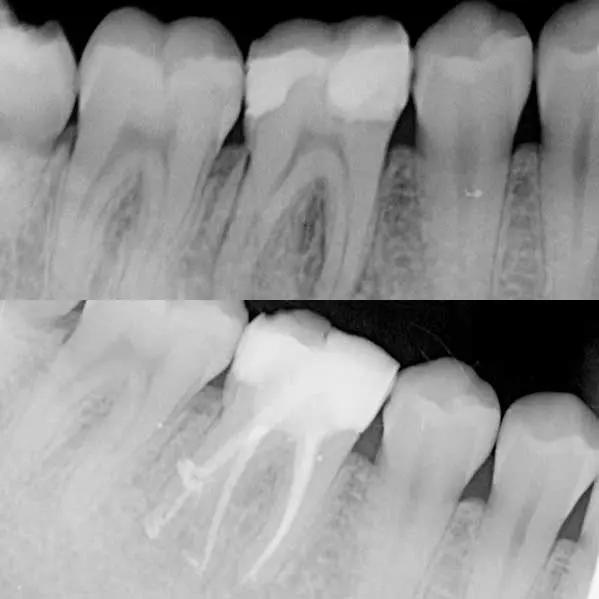

Los dientes son órganos únicos e irreemplazables, y con esta disciplina, tratamos de alargar su valiosa vida. Cuando tenemos un diente cuyo nervio ha sufrido un daño irreversible debido a caries, infecciones o quistes, podemos realizar una desvitalización y así lograr conservarlo.

Los dientes son órganos únicos e irreemplazables, y con esta disciplina, tratamos de alargar su valiosa vida. Cuando tenemos un diente cuyo nervio ha sufrido un daño irreversible debido a caries, infecciones o quistes, podemos realizar una desvitalización y así lograr conservarlo.